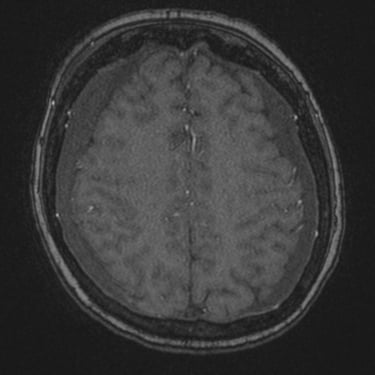

Hematoma Subdural Crónico | Diagnóstico por Resonancia Magnética

El hematoma subdural crónico es una acumulación lenta de sangre entre la duramadre y la superficie cerebral, generalmente secundaria a traumatismos leves en pacientes mayores o anticoagulados. Sus síntomas pueden incluir cefalea persistente, debilidad, alteraciones del lenguaje o cambios en el comportamiento. La resonancia magnética cerebral permite identificar con precisión la extensión y la antigüedad del sangrado, diferenciándolo de otras lesiones intracraneales. Este estudio es esencial para planificar el tratamiento, que puede requerir drenaje quirúrgico mediante trepanación o craneotomía mínima, permitiendo la recuperación neurológica progresiva y reduciendo el riesgo de recurrencia.